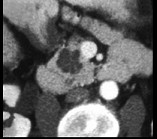

- 单项选择题患者,女, 57岁,上腹部隐痛半年余, CT片,最可能的诊断是 ( )

A、胰腺癌

B、胰腺脓肿

C、胰腺假性囊肿

D、胰腺囊腺瘤

E、胰岛细胞瘤